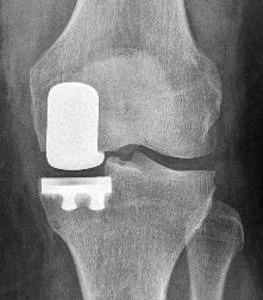

1. Totalna proteza kolena (podrazumeva zamenu donjeg kraja naktolenice i gornjeg kraja potkolenice)

Totalna proteza kolena